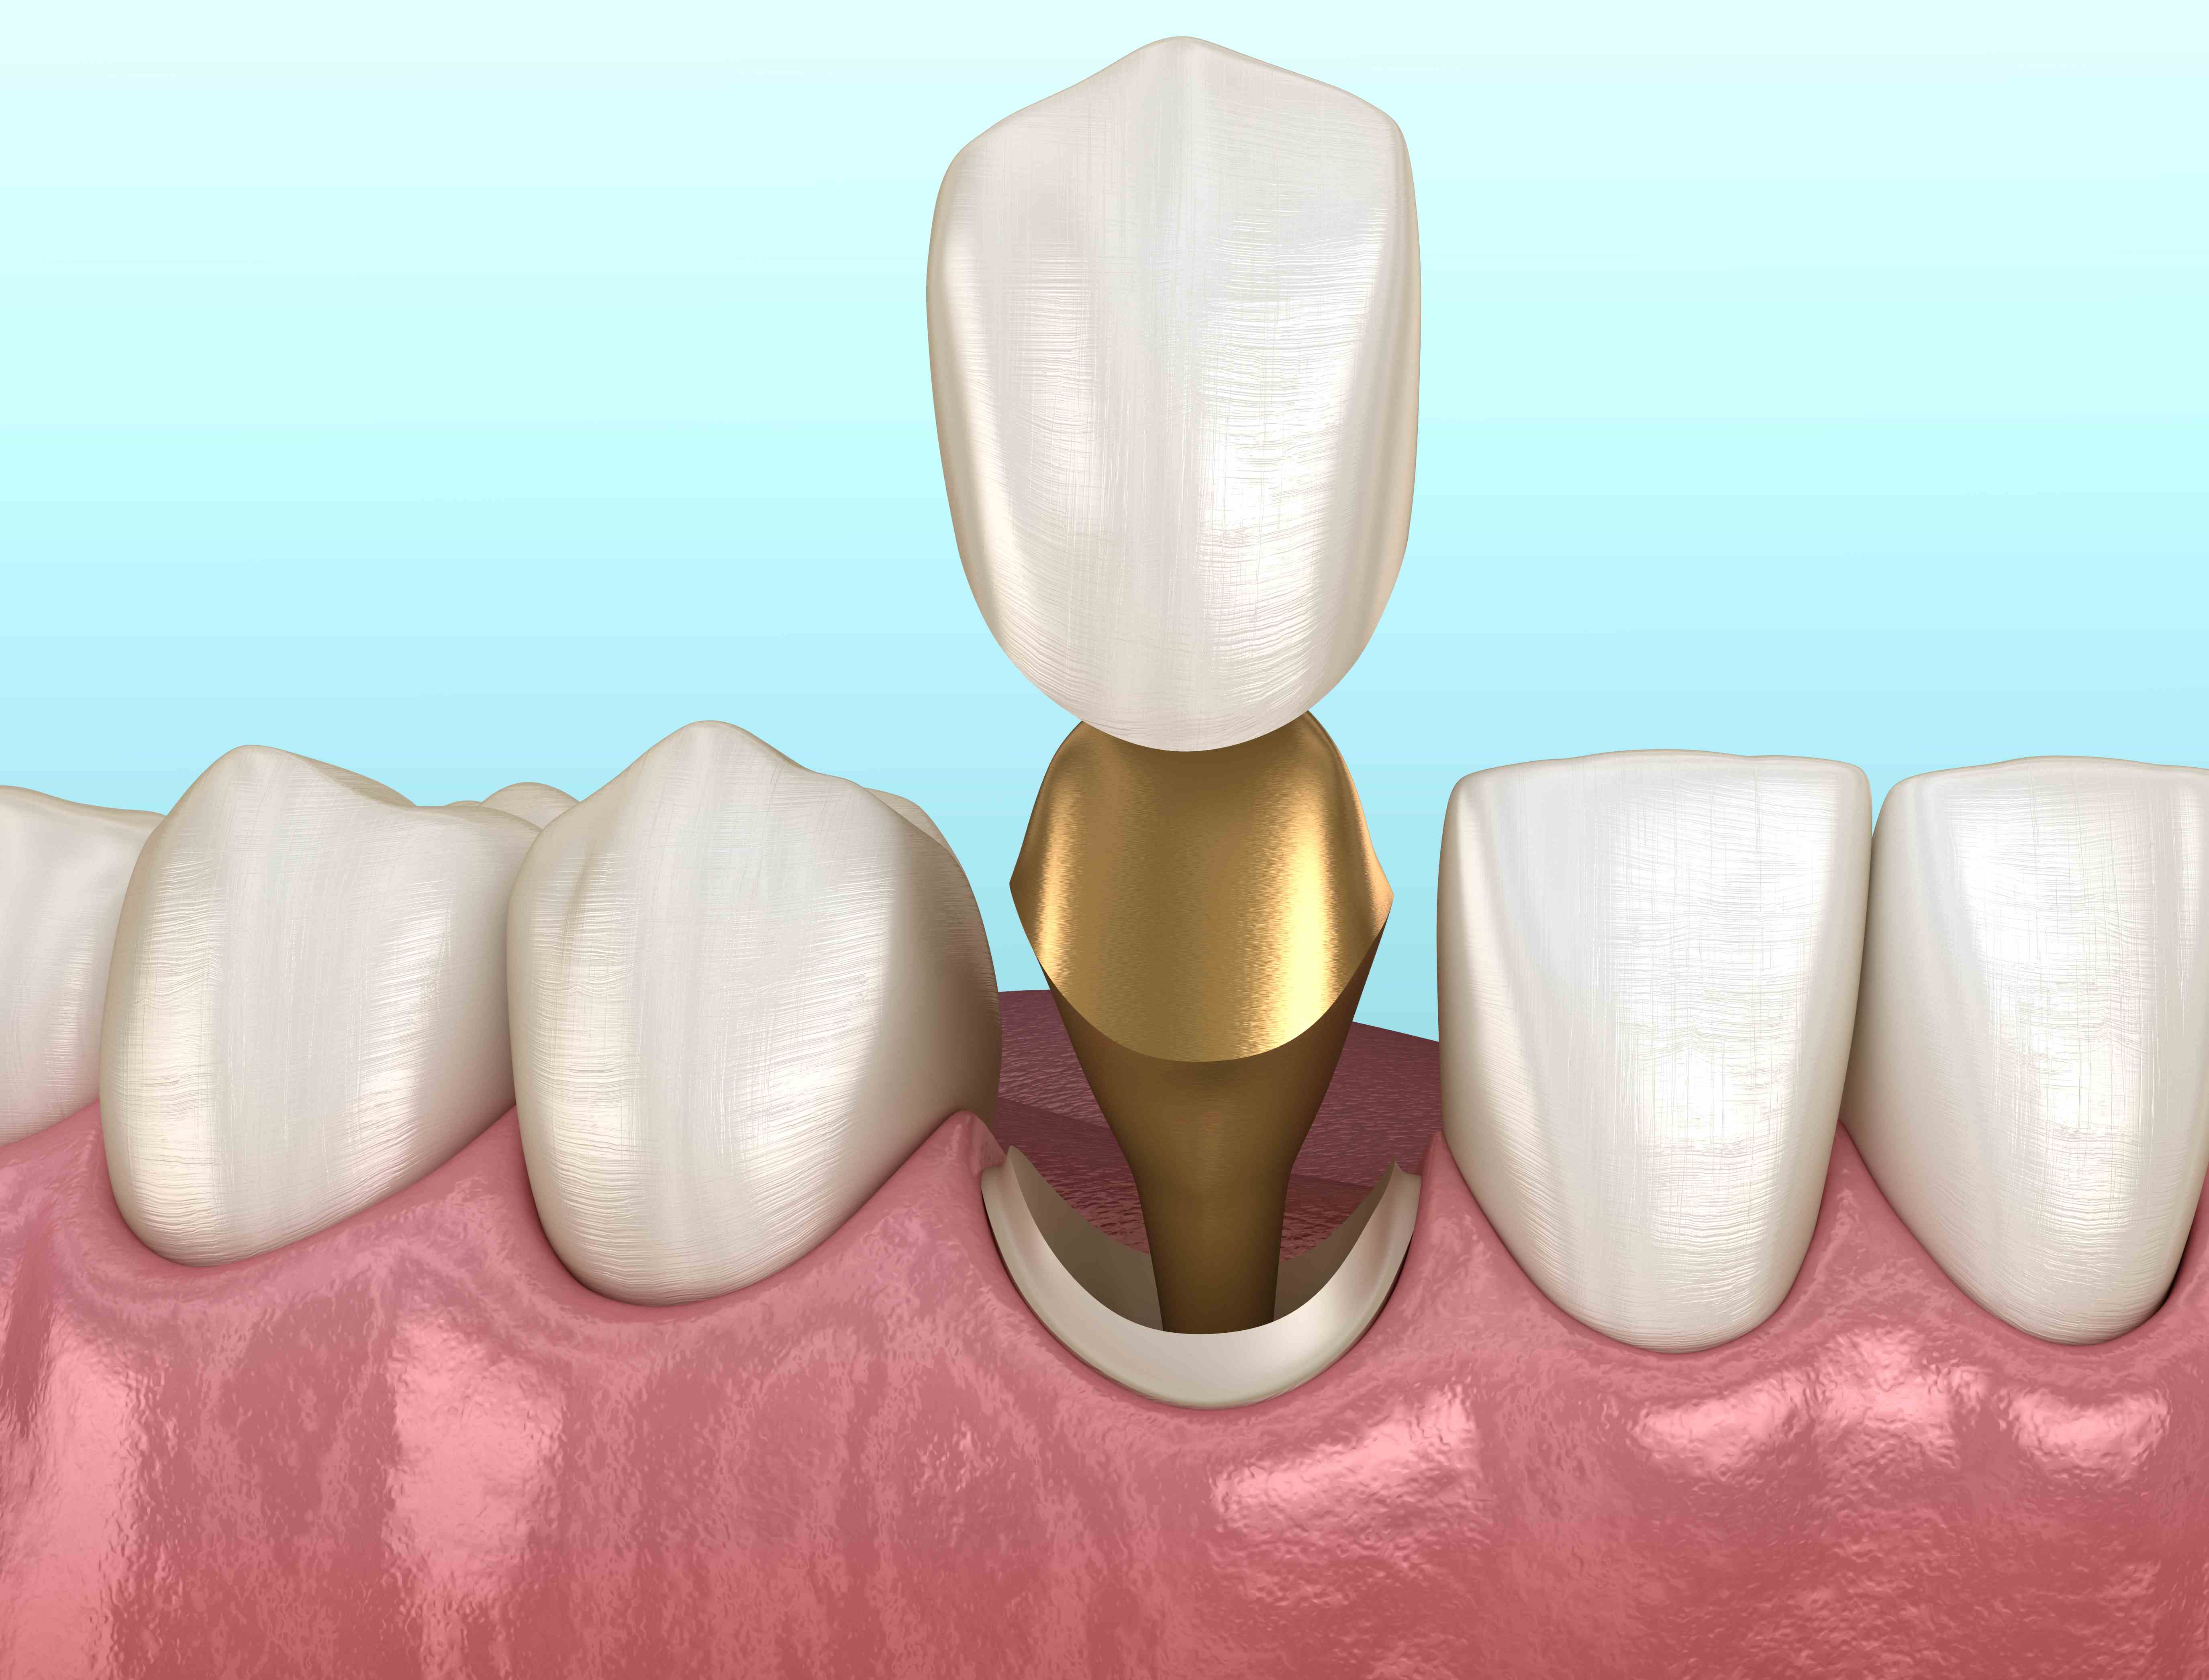

Культя зуба это

Культя зуба это 106 фото